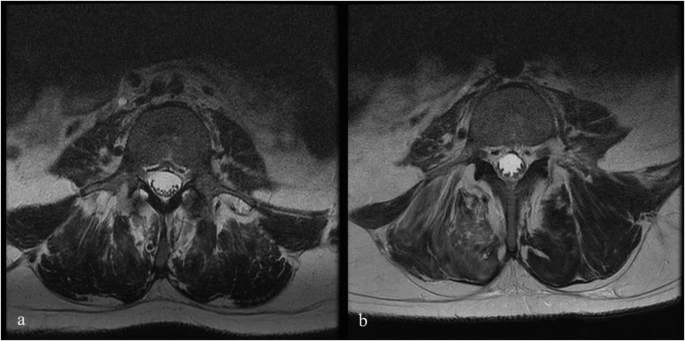

圖1:6號患者輸注前和輸注后MRI。

注射后血液和腦脊液檢查未發現異常。隨訪時MRI未見明顯變化;然而,在十名患者中,有八名檢測到馬尾神經根的叢集輕度增加,有或沒有結節性增強的證據。在經歷馬尾神經根聚集或強化的患者中,沒有發現明顯的臨床相關性。圖1顯示了患者6的輸注前和隨訪MRI,該患者L4-S1水平的馬尾神經根叢集輕度增加。表3突出顯示了所有患者干細胞注射前后的MRI變化。三名患者的SSEP有所改善。兩名患者與基線相比沒有任何變化,四名患者無法進行解釋,一名患者在整個研究期間具有正常的SSEP。表4突出顯示了SSEP 的發現和解釋。